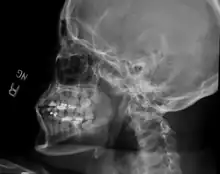

Sagittal section of the articulation of the mandible. | |

The joint involved with jaw dislocation is the temporomandibular joint (TMJ). This joint is located where the mandibular condyles and the temporal bone meet.[4][6] Membranes that surround the bones help during the hinging and gliding of jaw movement. For the mouth to close it requires the following muscles: the masseter, temporalis, and medial pterygoid muscle. For the jaw to open it requires the lateral pterygoid muscle.[4]